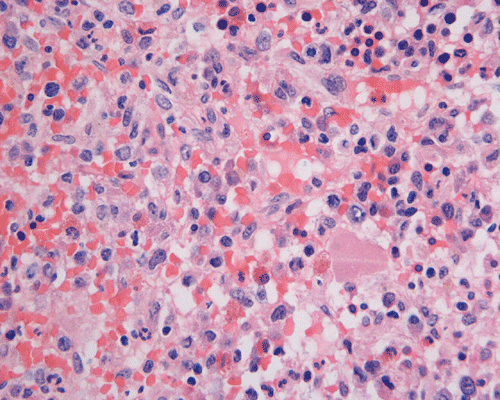

Clinical information: The patient was a 73 year-old man with an itchy skin rash, hepatosplenomegaly, and gastrointestinal bleeding. On admission, his complete blood count (CBC) showed an elevated white count (21,000/cm3) with 25% monocytes and 16% eosinophils, hemoglobin of 9.8 g/dL and 8,000 platelets/cm3. His 24-hour urine histamine was >200 mg/mL (ref 5.6-13.5 mg/mL). A bone marrow biopsy was performed and the representative photomicrographs are illustrated below:

| DIAGNOSIS: Aggressive systemic mastocytosis (WHO classification). |

The patient in the presented case was diagnosed with aggressive systemic mastocytosis, with documented bone marrow, liver and spleen involvement, and succumbed to his disease about two months after the presented biopsy.

Normal mast cells have a round or oval, centrally located nucleus with uniform distribution of dark purple granules in the cytoplasm. Mast cells are well demonstrated by toludine blue and Giemsa stains, and also by immunohistochemistry for CD 117 or tryptase. Napthol ASD chloracetate esterase also highlight mast cells specifically. Mast cells are also positive for CD45, CD33, and CD68 but these markers are less specific than tryptase. Bone marrow aspirations stained with Giemsa are most useful for recognizing atypia in mast cells. It should, however, note that Giemsa stain may be false negative in formalin fided tissue. Hallmarks of atypia in mast cells include spindling of mast cells, hypogranulation, uneven granule distribution, and nuclear lobulation. Recognition of the so-called mast cell granuloma, in which mast cell aggregrates are associated with lymphocytes and eosinophils can be helpful.

In the bone marrow, three morphologic patterns of mast cell accumulation have been recognized. Type I shows focal clusters of mast cells with preservation of bone marrow fat and other hematopoetic elements. The burden of mast cells is more in Type II and usually shows patchy clusters of mast cell replacing bone marrow in a hypercellular marrow background with osteosclerosis and fibrosis. Type III is diffuse replacement of the marrow space with mast cells, often with circulating mast cells in peripheral blood. It is also important to note that mast cells are easily over looked on routine H and E stain or are mistaken for histiocytes.

By flow cytometry, aberrant expression of CD 25 and CD 2 has been used to define an atypical population of mast cells. About 95% of systemic mast cell disease cases aberrantly express CD 25 and 70% aberrantly express CD 2.